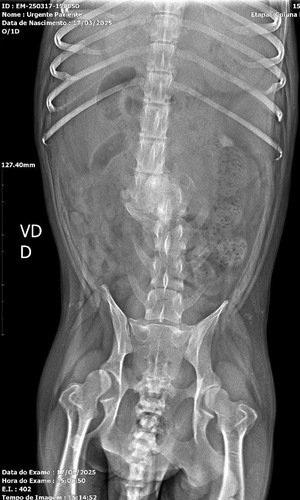

Então dia 17/10/2024 Preta se hospedou na minha clínica e certo dia percebi força em suas patas traseiras, e assim chamei uma fisioterapeuta veterinária para avaliar e na avaliação constatou presença de todos os reflexos para voltar a se locomover, não como antes, mas melhor do que está. Então cuidamos da preta tiramos todos os parasitas, curamos suas feridas e iniciamos as fisioterapias.Hoje fazem 5 meses que a Preta está conosco e virou nossa mascote da clínica. Fizemos um raio x nela recentemente e pela imagem da coluna não parece possível ela ter qualquer sensibilidade nas patas e cauda, então ela é realmente um MILAGRE! Do dia que ela chegou para hoje ela é uma nova cachorra mas sempre com a mesma vontade de viver e coração puro. Preta tem muita força nas pernas e ela AMA passear e a cadeirinha que ela tem hoje já está quebrando, nao é sob medida e ela já está machucando em alguns locais. Então para dar mais qualidade de vida para a Preta juntos vamos comprar uma cadeira de rodas sob medida e feita especialmente para ela, com pedais de fisioterapia que ajuda ela no movimento para andar também.Agradeço a todos que leram, siga preta no instagram @pretinha_dog_especial!